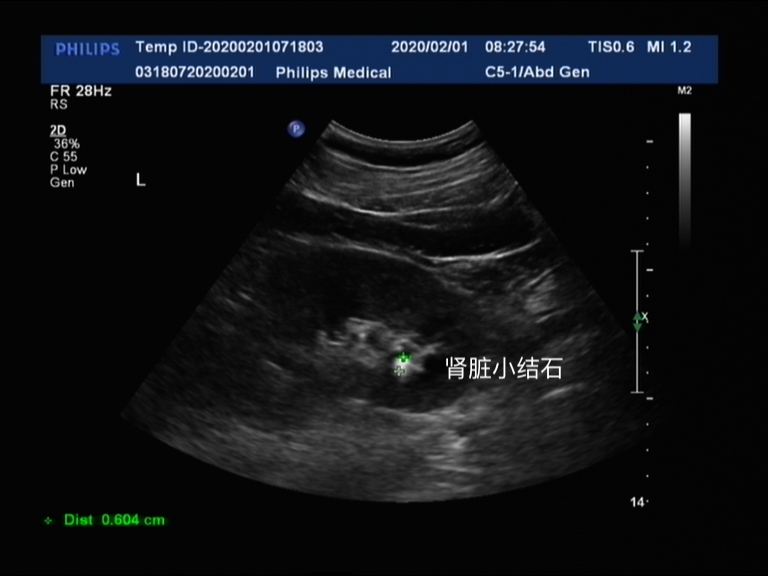

肾脏结石在彩超下是高亮的信号